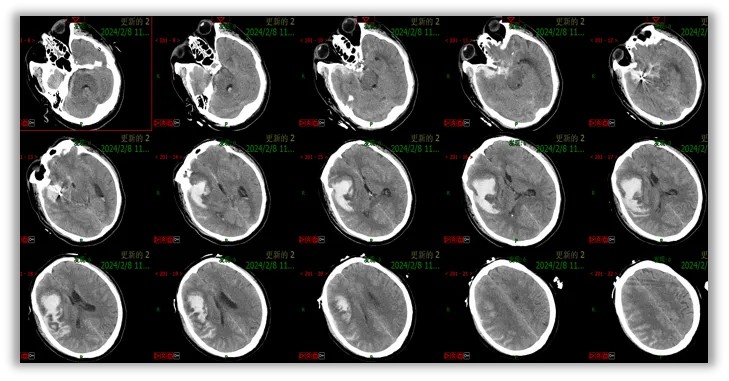

第1次手术顺利,次日复查CT,栓塞手术良好,按照原计划,进一步行血肿穿刺、抽吸、引流手术。

侧裂区血肿体积约25ml,侧裂区血管走形复杂,脑水肿高峰期,穿刺过程极易引发大出血。如何精准定位、穿刺血肿正中心?同时保护重要神经血管、并将脑组织的损伤降至最低?

工欲善其事必先利其器,我们采用神经导航,精准定位,避开重要的神经、血管,成功穿刺,一举成功。

手术顺利,引流管位置在血肿正中心,在挽救患者生命的道路上 ,又前进了一步。